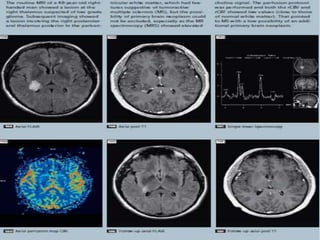

A 22-year-old man with centrally located

glioblastoma multiforme (WHO IV).

A, Tumor shows heterogeneous hyperintensity

with prominent peritumoral edema and/or

tumoral infiltration (arrow) on axial T2-

weighted SE image (2295/90). B, There is a

significant heterogeneous enhancement in

tumoral borders but not in peritumoral area

(arrow) on axial T1-weighted image (583/15).

C, Gradient-echo axial perfusion MR image

(627/30) with rCBV color overlay map shows

both high rCBVT value of 6.58 and rCBVP value of

2.21, which are consistent with HGGT.

Peritumoral increased rCBV (arrow) shows

tumoral infiltration outside the tumoral

margins, which is not perceptible on T2- and

contrast-enhanced T1-weighted images.

D, Time-signal intensity and gamma-variate

fitted curves from tumoral (red), peritumoral

(blue), and normal (purple) areas show

prominent decrease in signal intensity from

tumoral and peritumoral areas, when compared

with signal intensity of normal gray matter.